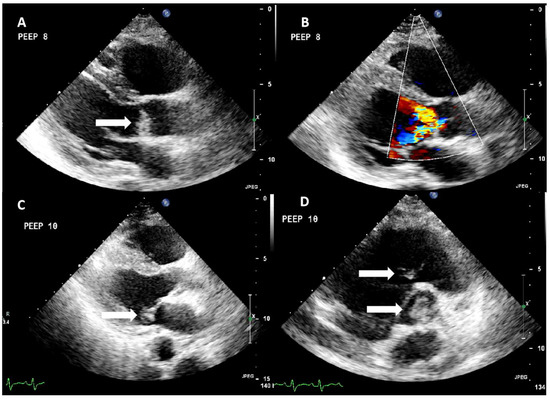

On the 10th day, the patient presented signs of right hemiparesis, and the results of the brain CT are presented in Figure 2. In Figure 2, images of the chest CT are also displayed.

Figure 2. Computed tomography findings. (A) Brain CT showing multiple ischemic lesions located in the left frontotemporolateral region (white arrow) and in the right frontal lobe. Effacement of the left lateral ventricle and displacement of the midline structures by 0.5 cm to the right. Trace of subarachnoid hemorrhage (white arrow). (B) Ischemic infarct at the periphery of the right kidney (right arrow). (C) Cavitary lesions in the right upper and (D) left lower lobe (black arrows).